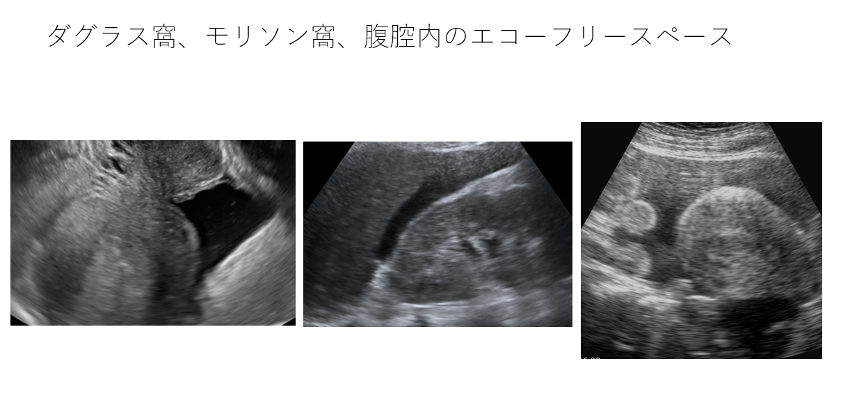

- ダグラス窩、モリソン窩、脾腎境界の異常所見

これらの場所にエコーフリースペースを認める場合や、子宮周囲にある腸管の蠕動運動の周囲に液体貯留があれば子宮破裂などが原因の腹腔内出血を疑う。